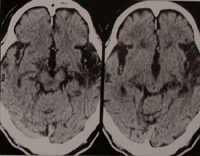

脳の血管が何らかの原因で狭窄(狭くなる)、閉塞(つまる)になるとその先にある脳細胞に血液が充分に行き渡らなくなります。脳細胞は血液に溶けている酸素と糖分で生きているのでこれが足りなくなると脳細胞は死んでしまいます。これが脳梗塞です。死んでしまった脳が手足の動きに重要な場所であれば手足の麻痺になりますし、言語に重要な場所であれば言語障害が出るのです。

脳血管がつまる原因には大きく分けて2つあります。

血栓症 |

動脈硬化によって徐々に血管の中が狭くなりついには閉塞するもの。症状は徐々に進行することが多く、時には一時的に麻痺や言語障害が出てその後改善する場合(一過性脳虚血発作といいます)もあります。 |

塞栓症 |

血液の固まりが血管の中を流れて脳血管に流れて閉塞させるもの。 |